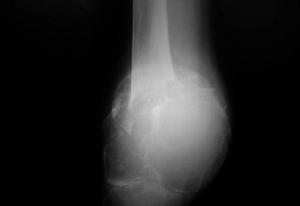

病理性骨折影像1、直接暴力直接作用使受傷部位發生病理性骨折,常伴有不同程度軟組織損傷。如車輪撞擊小腿,於撞擊處發生脛排骨骨幹病理性骨折。

2、間接暴力通過傳導、槓桿、鏇轉和肌收縮使肢體遠處發生病理性骨折,如跌倒時以手掌撐地,暴力向上傳導,依其上肢與地面的角度不同,力的傳導可致燒骨遠端病理性骨折或肱骨髁上病理性骨折,驟然跪倒時,股四頭肌猛烈收縮,可致髕骨病理性骨折。

5、X線檢查除正、側位X線攝片外,尚應根據傷情拍攝特殊體位相,如開口位(上頸椎損傷)、動力性側位(頸椎)、軸位(舟狀骨、跟骨等)和切線位(髕骨)等。複雜的骨盆骨折或疑有椎管內骨折者,尚應酌情行體層片或CT檢查。